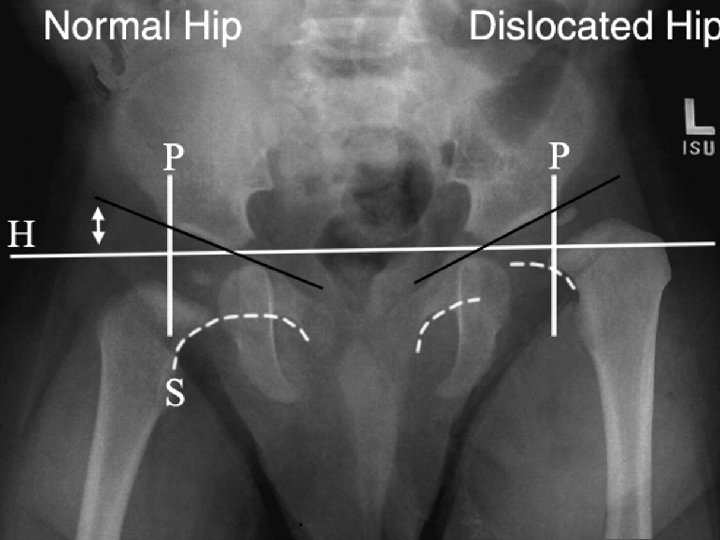

Plain Radiography From AP radiograph of the hip Hilgenreiner line : Horizontal line is drawn between each triradiate cartilage Perkin line: Lines Perpendicular to H line are drawn through the outer edge of the acetabulum (Perkin line), dividing the hip into 4 quadrants - Normally femur head lies in the lower inner quadrant Acetabular index or angle : H line and second line which extend from inner to outer edge of acetabulum -Normally less than 30 degree after age 6 months Shenton’s line : imaginary curved line drawn along the inferior border of the superior pubic ramus and along the inferomedial border of the neck of the femur. - Normally it’s smooth semicircular with no interruption